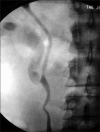

We present two cases of symptomatic lower pole moiety ureteropelvic junction obstruction (UPJO) in a partially duplicated collecting system that were successfully treated with minimally invasive endourologic procedures. In the first case, we performed retrograde endopyelotomy with the Acucise(R) ureteral cutting balloon device, and in the latter case, we performed percutaneous nephrolithotomy and antegrade endopyelotomy because of the presence of multiple renal stones. Subsequent intravenous pyelography confirmed marked resolution of the obstruction, and both patients remained asymptomatic during 1 year of follow-up.